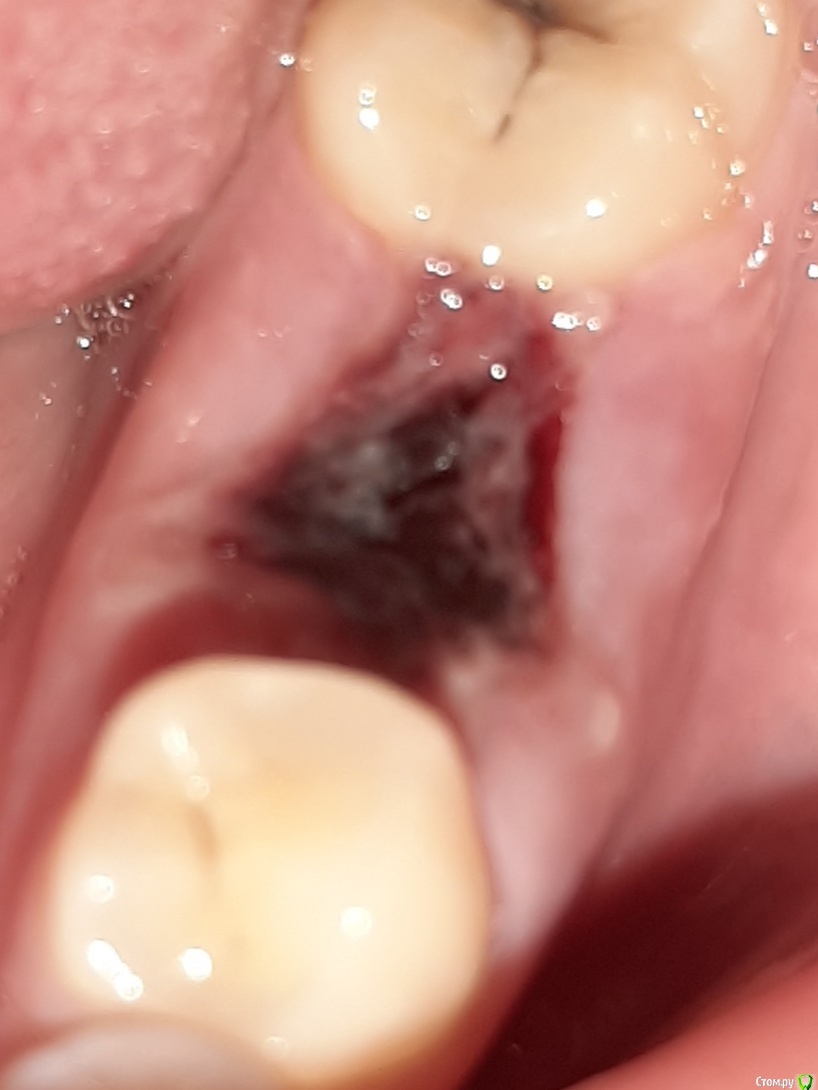

manyasha Опубликовано 4 марта, 2021 Автор Поделиться Опубликовано 4 марта, 2021 Поддеть зубочисткой или пинцетом. Не пытаться полоскать.еле как убрала, вот что получилосьэто нормально? Ссылка на комментарий

АнтонТЛТ Опубликовано 4 марта, 2021 Поделиться Опубликовано 4 марта, 2021 Нормально Ссылка на комментарий